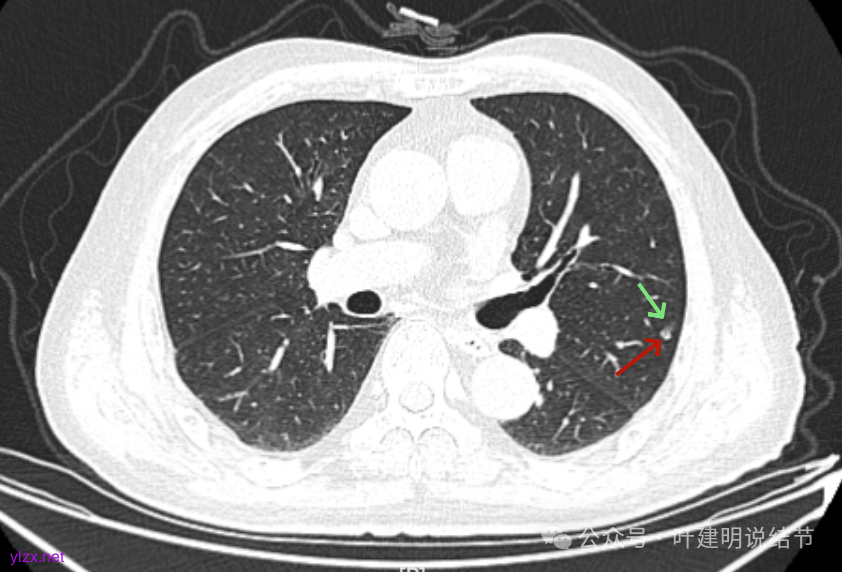

先来看2025年1月的影像:

病灶出现,有少许磨玻璃成分,整体轮廓较清,实性部分较为光滑。

有囊腔,表面不平,部分囊壁是磨玻璃成分。

病灶囊壁稍不均,多密度较高,表面欠平。

病灶整体的囊壁稍不均,靠内侧有磨玻璃成分。

囊壁不厚但密度较高。

囊腔内壁稍显不光滑,有少许突起于囊腔内。

上图也见囊腔内壁有突起,此层囊壁大部分呈磨玻璃密度。

边缘区是淡磨,内壁少许突起。

冠状位见病灶囊壁不均,表面不光滑,囊腔内壁也不太平整。

矢状位见病灶囊壁有结节状高密度。

右下叶也有囊腔灶。

两肺其他地方多处肺大泡。

左肺上叶红色这处是囊腔型病灶,囊壁略不均,似有微小血管进入囊壁,对比2023年4月整个囊腔来讲有扩大,需要考虑囊腔型肺癌的可能性大。右侧蓝色的并不是典型囊腔型肺癌的表现,再加上两肺绿色这些慢支肺气肿与肺大泡的影像,右侧的就更加不确切,至少近期不能够考虑右侧也要开刀的事情。其实左侧的主病灶相对于其他表现更典型的囊腔型肺癌来说,由于囊壁密度偏高,也不是百分百必定是肺癌。我的想法还是先等脑梗情况稳定,并且间隔4~6个月复查病灶再有进展在考虑单孔胸腔镜下局部切除就可以。淋巴结可以考虑采样,但一般不至于阳性。破是不会切破的。消融不建议,囊腔灶更难通过穿刺获得病理依据,况且东西在边上,能局部楔切,当然首选手术。意见供参考!